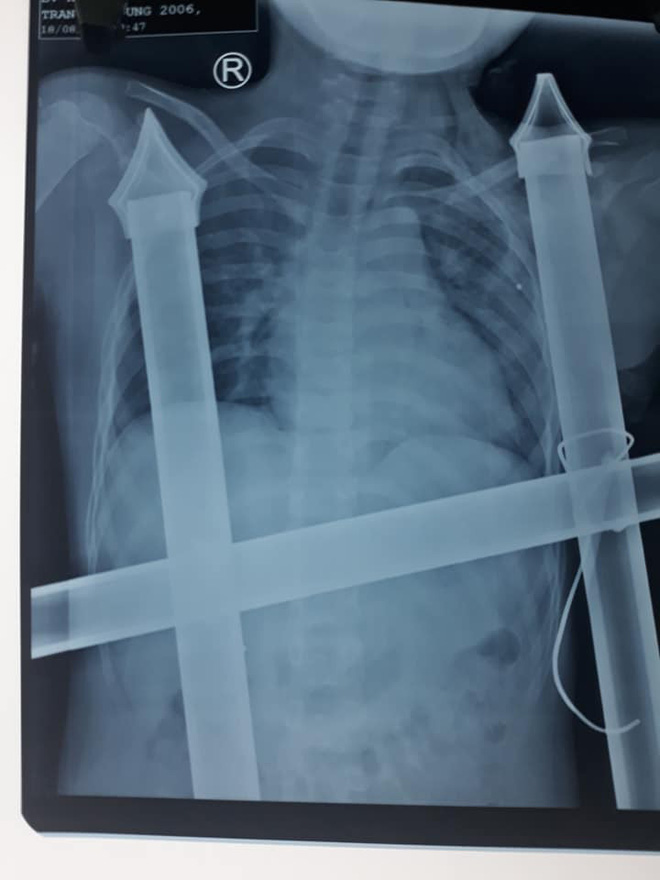

24/08/2019 14:09Trèo cây ngã xuống, cậu bé 13 tuổi bị chông hàng rào đâm xuyên dọc ngực

Ngày 23/8, bác sỹ tại Bệnh viện Hữu nghị đa khoa Nghệ An cho biết, phía bệnh viện vừa cứu sống một bé trai bị chông hàng rào sắt đâm xuyên vào người.

Trước đó vào khoảng 21h ngày 17/8, em Trần Anh Dũng (13 tuổi, trú huyện Quỳnh Lưu) trèo cây chơi đùa cùng bạn. Trong lúc trèo cây, Dũng bị ngã khiến chông nhọn hàng rào đâm xuyên vào ngực, cơ thể treo lơ lửng trên hàng rào cao.

Phát hiện sự việc, người thân đã lập tức ra cắt đoạn hàng rào này và đưa em Dũng vào Bệnh viện cấp cứu.

Thời điểm nhập viện, Dũng bị phần chông nhọn của hàng rào dài hơn 10cm đâm xuyên dọc ngực trái. Một phần chông nhọn đã chạm đến nền sọ của bệnh nhân Dũng.

Sau khi chụp chiếu, các bác sỹ đã tiến hành phẫu thuật tháo đầu sắt nhọn ra ngoài và xử lý các tổn thương ở vết thương.

"May mắn là vật sắc nhọn không làm mạch máu lớn và nội tạng bị tổn thương. Bệnh nhân bị đứt cơ ngực lớn, cọc sắt hàng rào tạo nên đường hầm trong khoang ngực kéo dài trên 10cm.

Chúng tôi đã rút được dị vật ra khỏi cơ thể cậu bé an toàn. Đồng thời, lau rửa, sát trùng vết thương, dẫn lưu đường hầm, khâu cơ ngực lớn và da liền lại", BSCKI. Hồ Thái Phúc (khoa Phẫu thuật Tim mạch lồng ngực) cho biết.

Đến thời điểm hiện tại, bệnh nhân Dũng đã hồi phục và có thể xuất viện trong thời gian tới.